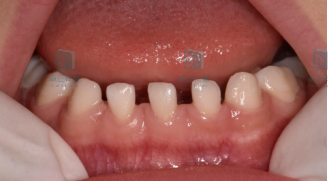

牙缝稀稀拉拉,原来是缺了几颗牙

有些小朋友牙缝很大,是因为牙齿数目不足,也就是先天缺牙。先天缺牙有遗传倾向少数情况跟全身疾病相关

图片

乳牙的先天缺牙一般不需要干预,恒牙先天缺牙如果影响咀嚼或美观,建议检查后根据具体情况决定是否需要处理。

不过并不是牙缝稀稀拉拉的小朋友都有缺牙的情况,比如大多数乳牙列都是有一些散在牙缝的,这是正常现象,家长们不必太紧张。